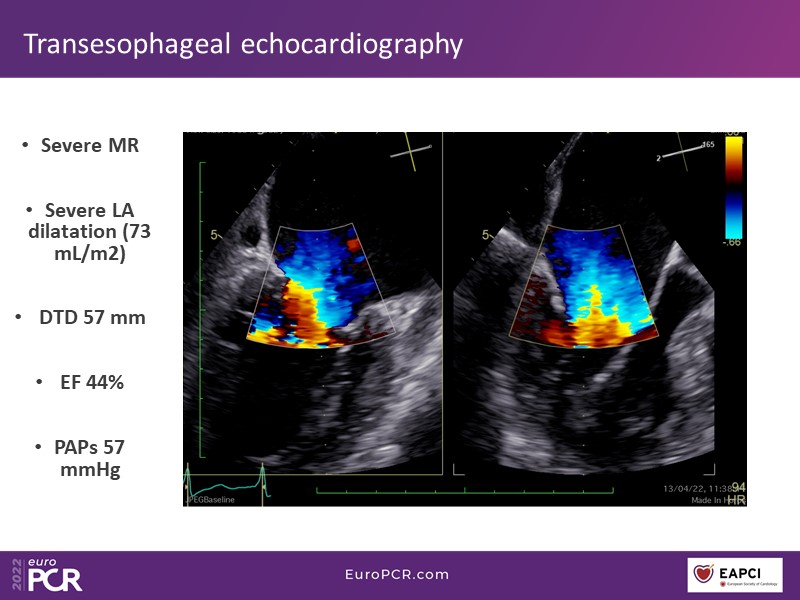

Watch this EuroPCR 2022 session to learn the key steps in transcatheter mitral valve repair and transcatheter aortic valve implantation procedures.

Follow step by step how to optimally access and close venous large bore access sites using suture mediated vessel closure devices, and learn about the key differences compared with arterial large bore access.